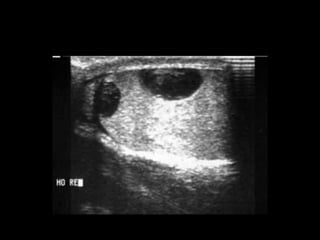

• USG S-80%, E-85%

Diagnostico

• Clinica

• USG

• USG DOPPLER